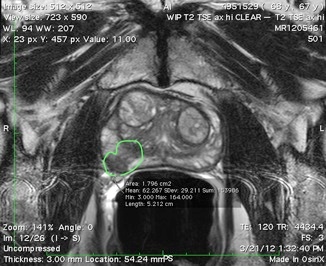

3T-MRI-Image-1

The 3T MRI image on the left clearly shows an obvious tumor (outlined in green). MRI guided fusion biopsy revealed Gleason grade 7 cancer. The ultrasound exam did not detect this cancer.